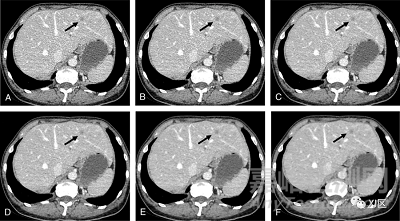

最近,基于神經(jīng)網(wǎng)絡(luò)的深度學(xué)習(xí)的圖像重建(DLIR)算法正在出現(xiàn):GE Healthcare的TrueFidelity(TF)和Canon Medical Systems的Advanced Intelligent Clear-IQ Engine(AiCE)。圖2、3和4顯示了用FBP、ASIR-V、TF和iDose4在不同水平上重建的CT掃描的例子。

圖2 用不同水平的ASiR-V算法重建的CT圖像的比較。一位57歲女性,患有結(jié)直腸癌,伴有單肝轉(zhuǎn)移,腹部靜脈期軸位CT掃描(黑色箭頭)。掃描是在100 kVp下通過管電流調(diào)制獲得的(mAs范圍,99–170);用(A)濾波反投影(FBP)和ASiR-V在20%(B)、40%(C)、60%(D)、80%(E)和100%(F)強(qiáng)度重建原始數(shù)據(jù)。隨著ASiR-V強(qiáng)度水平的增加,圖像噪聲逐漸減少,而低衰減轉(zhuǎn)移仍然可見。此外,IR在對比度可檢測性和噪聲降低方面的改進(jìn)導(dǎo)致了腹部動脈和靜脈分支的更好描繪,甚至是遠(yuǎn)端小血管的更好描繪。